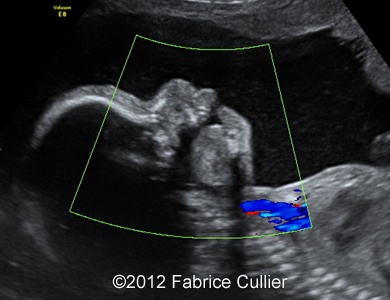

Images 1, 2: A transversal plane of the skull, too round (Brachycephaly).

1A

1B